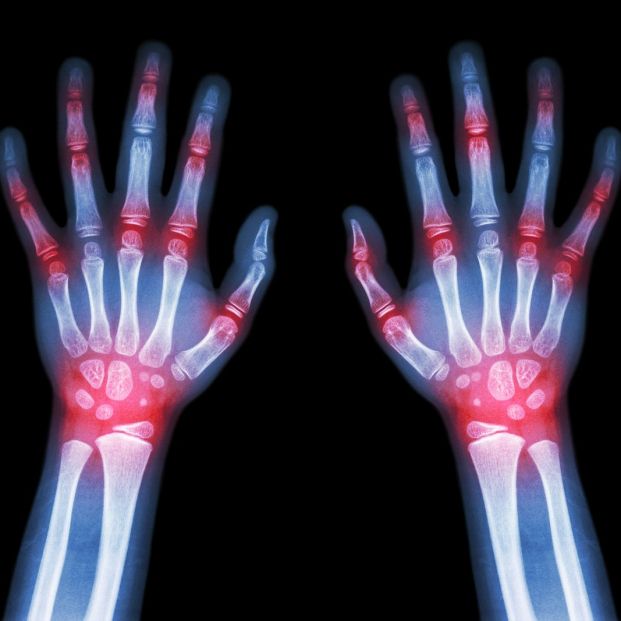

La artritis reumatoide es una enfermedad inflamatoria, autoinmune y crónica que afecta a aproximadamente el 1% de la población mundial, siendo más prevalente en mujeres. Esta enfermedad no solo compromete las articulaciones, sino que también puede tener efectos adversos en otras partes del cuerpo.